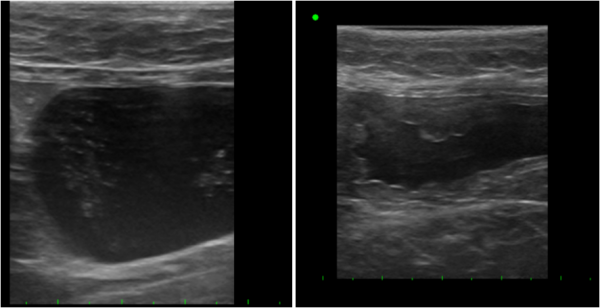

정상 방광(좌) / 내원한 환자의 방광(우)

이 경우 대부분은 감염성을 의심할 수 있지만 고양이에서는 다릅니다.

당연히 검사 결과 세균 감염은 확인되지 않았습니다.

하지만 아이는 분명히 통증을 느끼고 있었고,

화장실을 반복적으로 들락거리며 스트레스를 받고 있는 상태였습니다.